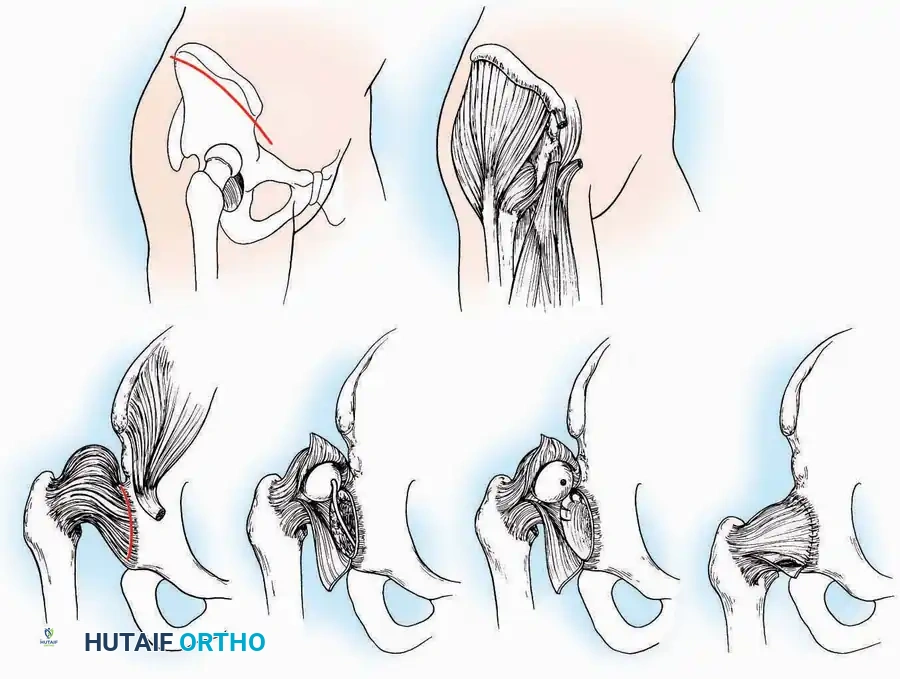

Anterolateral Approach

The anterolateral approach is widely considered the "universal incision" for the foot and ankle. It provides unparalleled access to the ankle joint, the talus, and the majority of the tarsal articulations, while safely avoiding the major anterior neurovascular bundle. The only tarsal joints inaccessible via this route are the naviculocuneiform joints (specifically the medial and intermediate).

Indications: Total talectomy, triple arthrodesis, ankle arthrodesis, and open reduction of complex talar neck fractures.

Surgical Technique:

* Incision: Begin over the anterolateral aspect of the leg, medial to the fibula and 5 cm proximal to the ankle joint line. Carry it distally over the joint, crossing the anterolateral aspect of the talar body and the calcaneocuboid joint, terminating at the base of the fourth metatarsal.

* Superficial Dissection: Incise the superficial fascia and the superior and inferior extensor retinacula down to the periosteum of the tibia and the ankle joint capsule.

* Vascular Ligation: This trajectory usually requires the identification and ligation of the anterolateral malleolar and lateral tarsal arteries.

* Nerve Protection: Retract the skin edges carefully. Identify and protect the intermediate dorsal cutaneous branches of the superficial peroneal nerve (SPN), which frequently cross the distal aspect of this incision.

* Muscle Management: Identify the origin of the extensor digitorum brevis (EDB) muscle on the lateral calcaneus. Divide it in the direction of its fibers, or detach its origin entirely and reflect it distally to expose the subtalar and calcaneocuboid joints.

* Deep Exposure: Retract the extensor digitorum longus (EDL) tendons, the dorsalis pedis artery, and the deep peroneal nerve (DPN) medially. Incise the anterior ankle capsule to expose the tibiotalar joint.

* Tarsal Exposure: Expose the talonavicular joint by dissecting deep to the extensor tendons and incising its capsule transversely. Continue laterally through the capsule of the calcaneocuboid joint. By excising the fat pad within the sinus tarsi (lateral and inferior to the talar neck), the posterior facet of the subtalar joint is brought into direct view.